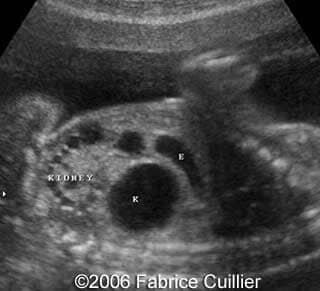

This is a 24- year-old-primigravida scanned at our unit at 21 weeks. During the first trimester, the nuchal translucency and the triple test were normal. At the end of the second trimester, the sonographer diagnosed a left polycystic kidney. The right kidney was normal with a normal corticomedular differentiation. The bladder was also normal. The patient refused additional investigations. We performed a scan at 21 weeks. The ultrasound findings were:

• normal right kidney with a normal corticomedular differentiation

• an abnormal polycystic left kidney (34 X 17 mm) with an abnormal corticomedullar differentiation. This kidney was on the lumbar fossa.

Transverse view of the normal right kidney and the abnormal left kidney